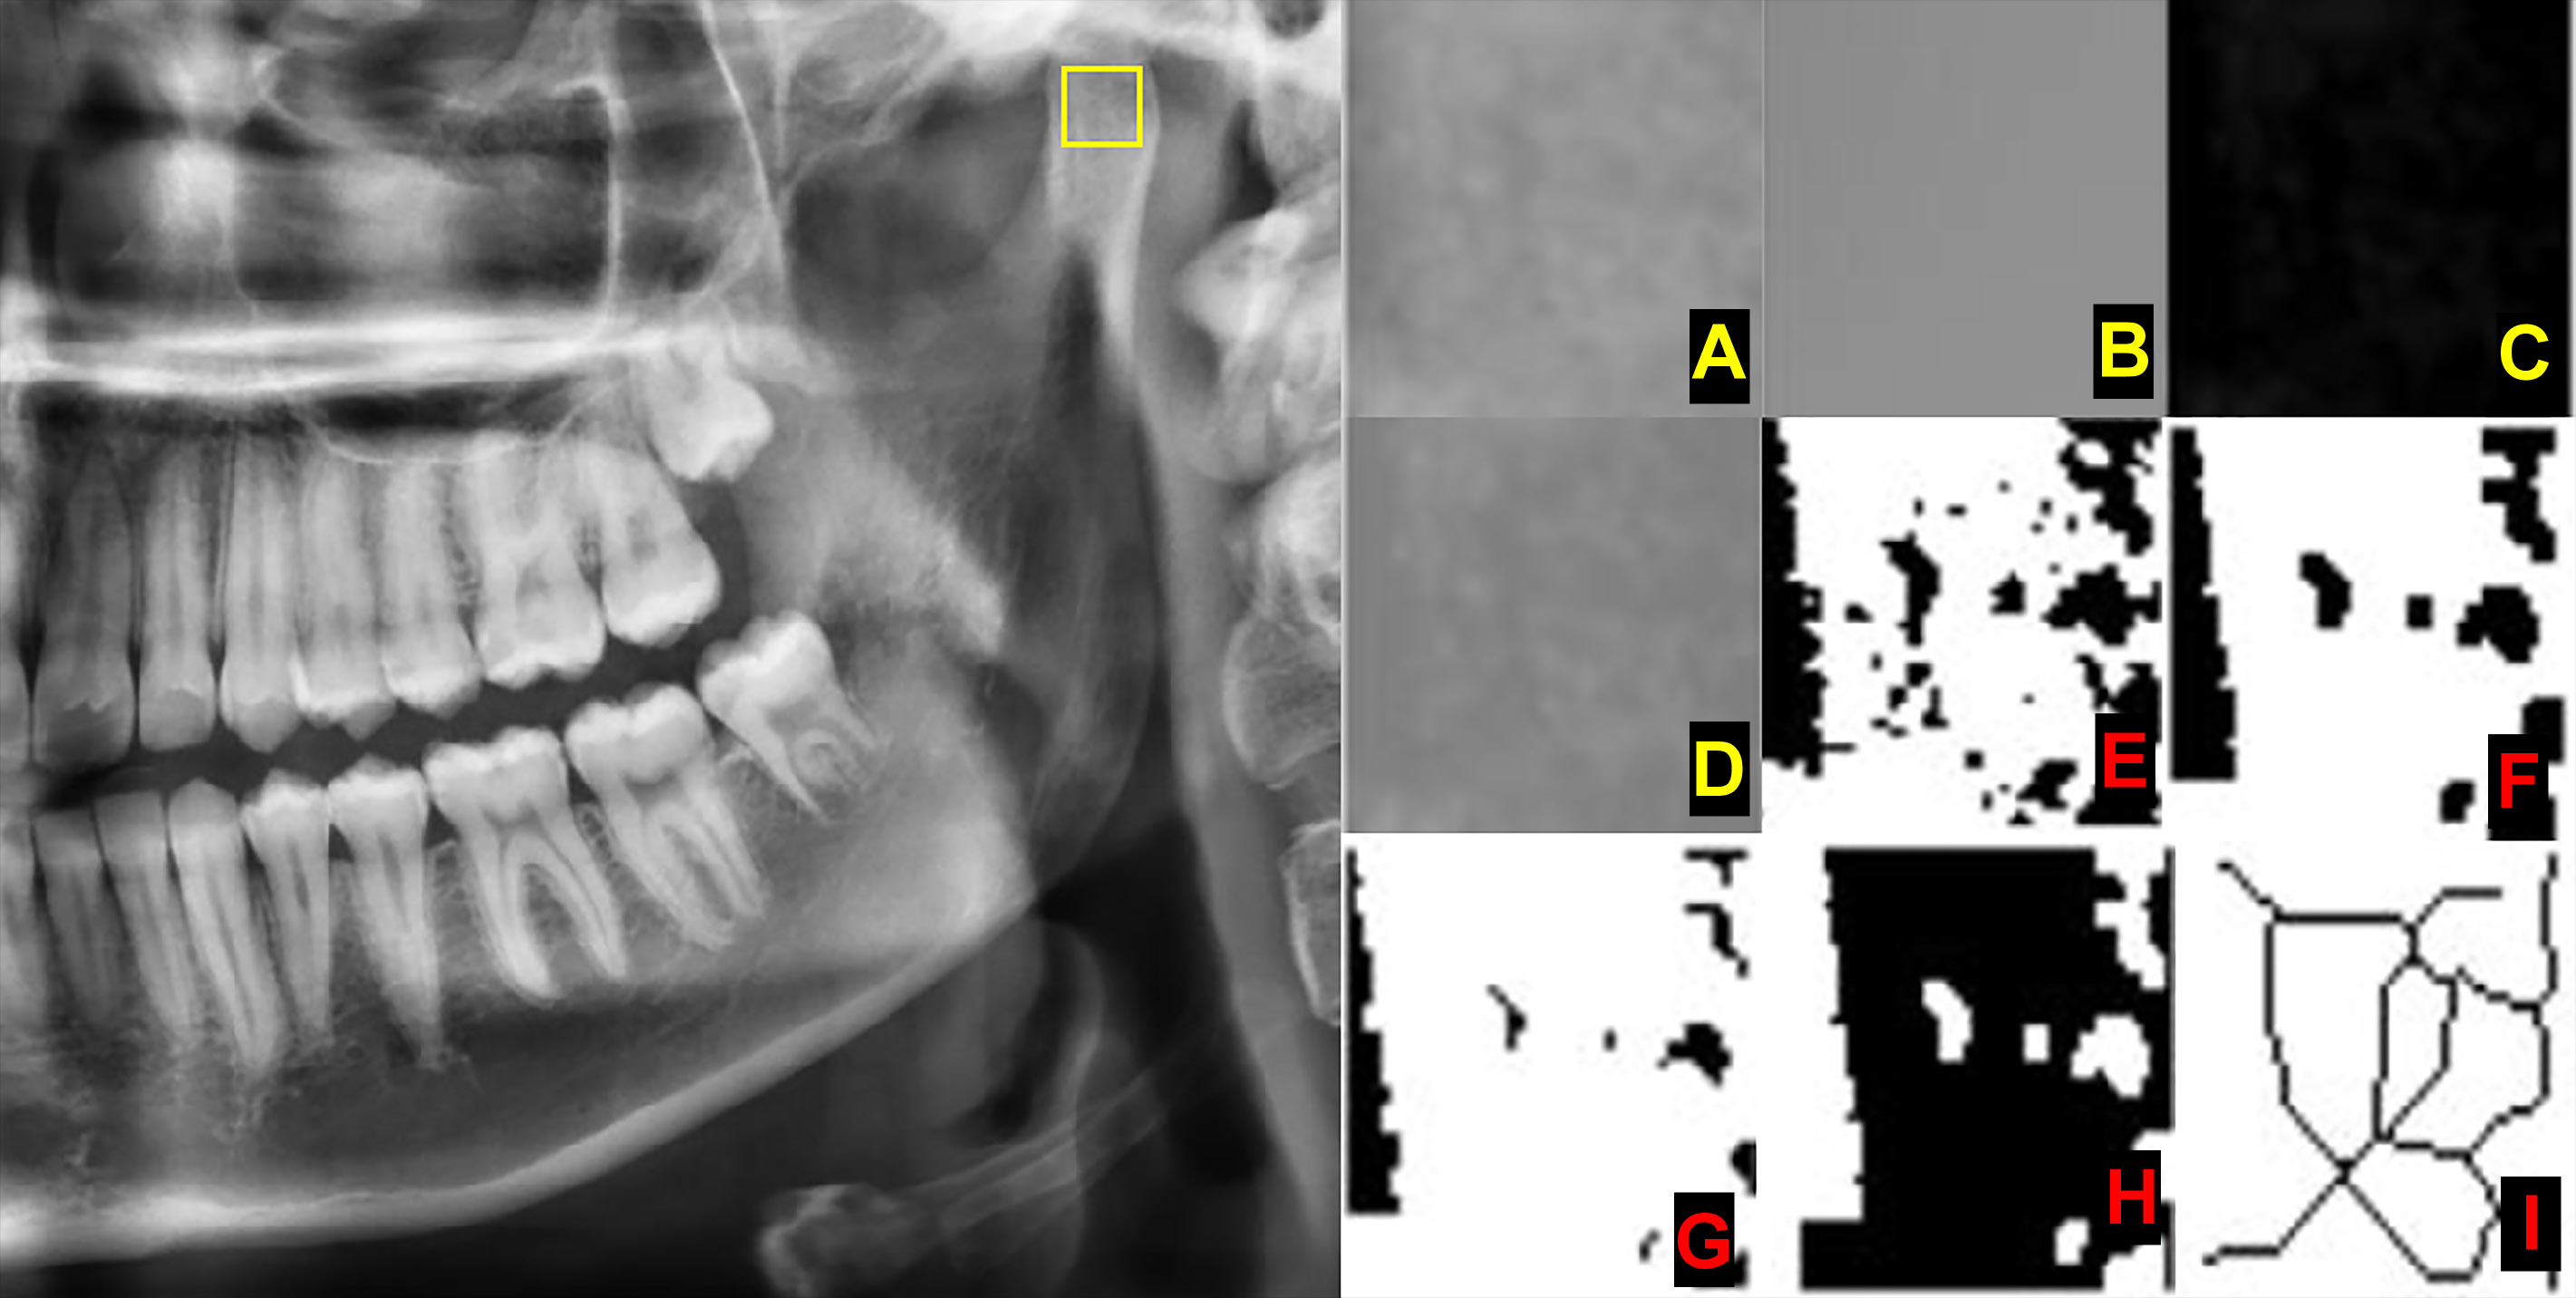

All digital panoramic radiographic images were exported in the JPEG (Joint Photographic Experts Group) file format at 1,600 × 887 pixels. The exported images were analyzed with the ImageJ software, v. 1.3 (National Institutes of Health, Bethesda, USA; https://imagej.nih.gov/ij/). Fractal dimension analysis was performed according to White and Rudolph’s box-counting method.18

Three different regions of interest (ROIs) were determined. Each ROI on both the left and right sides was measured, and the obtained values were used for statistical analysis (Figure 2):

– ROI_1 – a square of 30 × 30 pixels in the geometric center of the subcortical area in the mandibular condyle;

– ROI_2 – a square of 30 × 30 pixels in the supracortical area of the angulus mandibulae; and

– ROI_3 – a square of 30 × 30 pixels in the trabecular bone area, distal to the root of the first or second premolar, above the mandibular canal. This area was determined to detect the FD value in the mandibular corpus. To standardize the measurement in this area, as presented in Figure 2, it was made from the premolar tooth which did not have any lesion in or around its apical part.

The chosen ROI was cropped and duplicated (Figure 3A). The image was blurred with the Gaussian filter to remove the large-scale variations of brightness related to object thickness or the soft tissue (Figure 3B). The overly blurred image was subtracted from the initial image (Figure 3C). A gray value of 128 was added to each pixel location, resulting in an image with a mean pixel value of 128 (Figure 3D). With this step, certain variations, such as trabeculae and bone marrow, become visible. The image was then made binary with the threshold function, resulting in an image of 2 values – black and white (Figure 3E). White areas represented trabeculae, while black areas represented bone marrow. Then, the image was eroded and dilated, reducing the noise (Figure 3F and Figure 3G). The resultant image was inverted so that the areas representing trabeculae were set to black (Figure 3H). The image was further eroded with the skeletonization function until the only centerline of the pixels was present (Figure 3I). The FD value was calculated with the box-counting function. The image was covered with squares of 2-, 3-, 4-, 6-, 8-, 12-, 16-, 32-, and 64-pixel-sized boxes. The number of boxes involving trabeculae and the total count of the boxes were calculated for each box size. The FD value was measured from the slope of the line in the logarithmic scale graph of the obtained values.